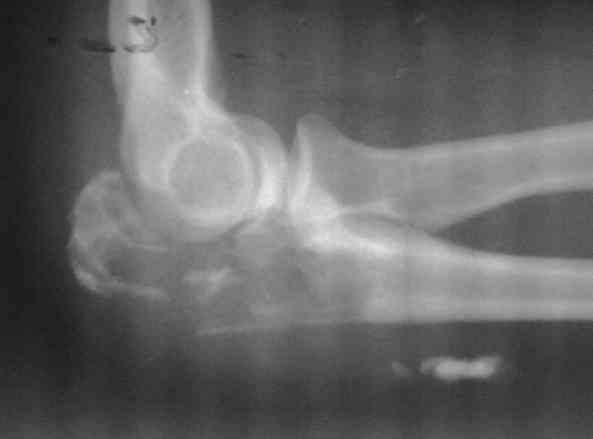

патологический перелом локтевого отростка

Женщина 39 лет, патологический перелом локтевого отростка,при гистологии ОБК.

Помощь в определении тактики

1. артродез

2. протезирование ( возможно-ли, каким протезом (стандарт, онкологический) прогноз восстановление функции )